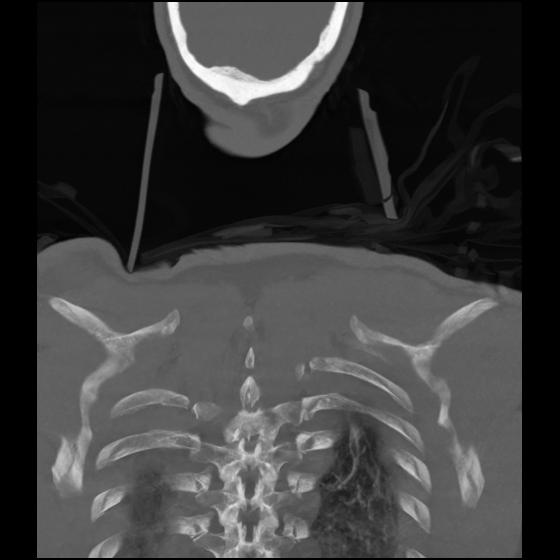

23 ANGIO,CE,Cor-MIP,5.000,ANGIO,Cor-MIP,